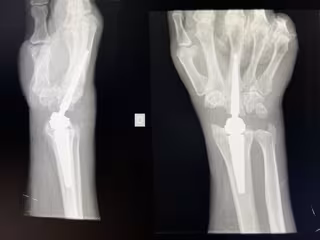

Vithas Madrid Aravaca implanta con éxito una prótesis de muñeca que elimina el dolor y mantiene la movilidad y fuerza

Prótesis de muñeca

Prótesis de muñeca - VITHAS

El Hospital Universitario Vithas Madrid Aravaca ha implantado una novedosa prótesis total de muñeca que sustituye a la articulación dañada en diez pacientes que tiene por objetivo eliminar el dolor y recuperar la movilidad y la fuerza.